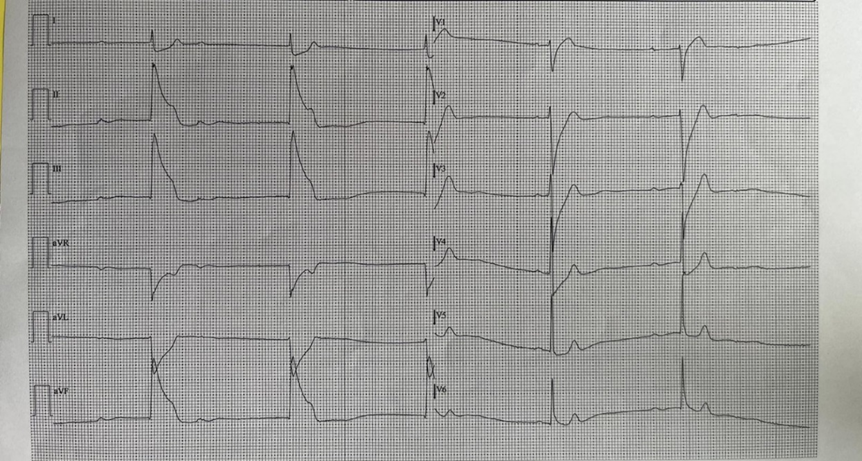

We present the case of a 56-year-old patient, affected by arterial hypertension and with no cardiac history, who called the Emergency number because of an episode of resting angina at home. When emergency vehicles arrive the patient was initially asymptomatic and electrocardiogram was normal. For recurrence of chest pain, a second ECG tracing was performed and it highlighted a second degree atrio-ventricular block, Mobitz 2, ST-segment elevation in the infero-lateral and sub-ST segment in leads V1-V2 (Figure. 1). The patient was then taken to the Hemodynamics of our Hospital for urgent coronary angiography. The exam did not find significant coronary atherosclerosis affecting the epicardial coronary arteries (only a 30-40% stenosis of the right coronary artery in the middle section was described). At the transthoracic echocardiogram performed in the Coronary Unit, significant valvular defects were excluded, the left ventricular ejection fraction (LVEF) was preserved with only a mild hypokinesia of the inferior-posterior wall. In the suspicion of vasospastic angina on the documented atherosclerotic plaque of the right coronary artery, Diltiazem i.v. was introduced into therapy and then orally. In the following 48 hours the patient experienced two different episodes of angina with an ECG tracing compatible with inferior-STEMI and third degree atrioventricular block (Figure. 2). The symptoms rapidly reduced after intravenous nitroglycerin administration, with prompt restoration of sinus rhythm (Figure. 3). Enzyme curve was not significant (hs-TnT 10 ng/L, Ck-Mb 3.4 mcg/L). During the hospitalization the therapy with calcium channel blocker was up-titrated and nitrate was also introduced, without further anginal episodes or major brady-arrhythmias. Considering the mild coronarosclerosis and the high lipoprotein-A levels (Lp(a) 85 mg/dl), we decided to maintain the therapy with acetylsalicylic acid and the Rosuvastatin/Ezetimibe combination. After 5 days the patient was transferred, asymptomatic and with good haemodinamic status, to a cardiac rehabilitation facility. At the follow-up visit in the Day Hospital Ambulatory, 3 months later, the echocardiogram was normal, and the drug therapy was well tolerated. No new arrhythmic events were detected at the control Holter ECG.

Figure. 1: ECG performed by the Emergency Service at first contact with the patient experiencing chest pain